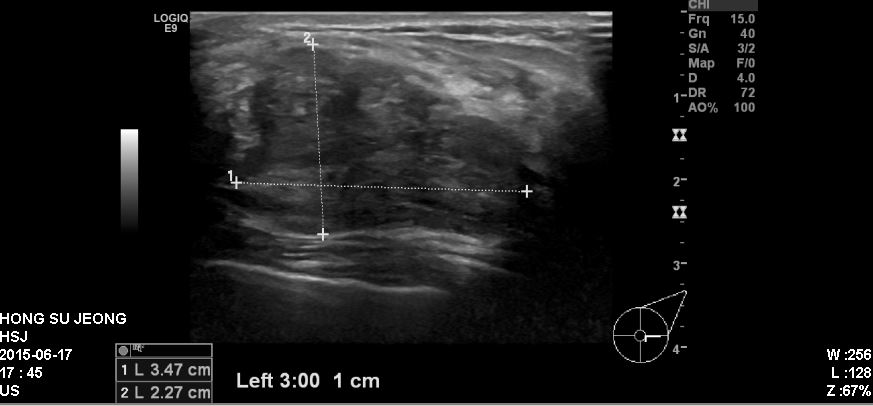

좌측유방에 만져지는 멍우리로 내원하신 50대 환자분이십니다.

본원에서 좌측3시방향에 혹을 조직검사 시행하였고

결과상 유방의 점액암종으로 확인되었습니다.